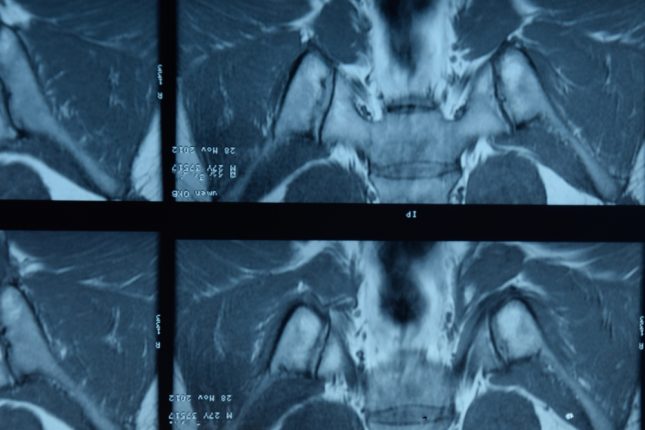

דלקת חוליות מקשחת